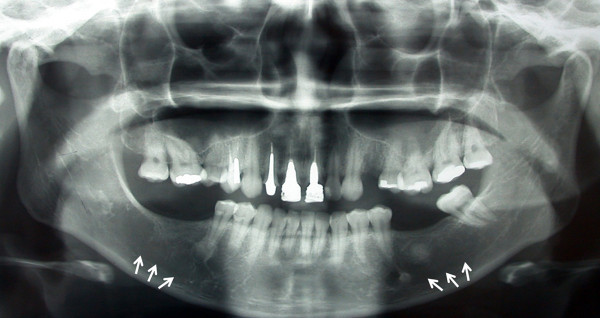

What is this?

idiopathic osteosclerosis

What are radiographic features of idiopathic osteosclerosis?